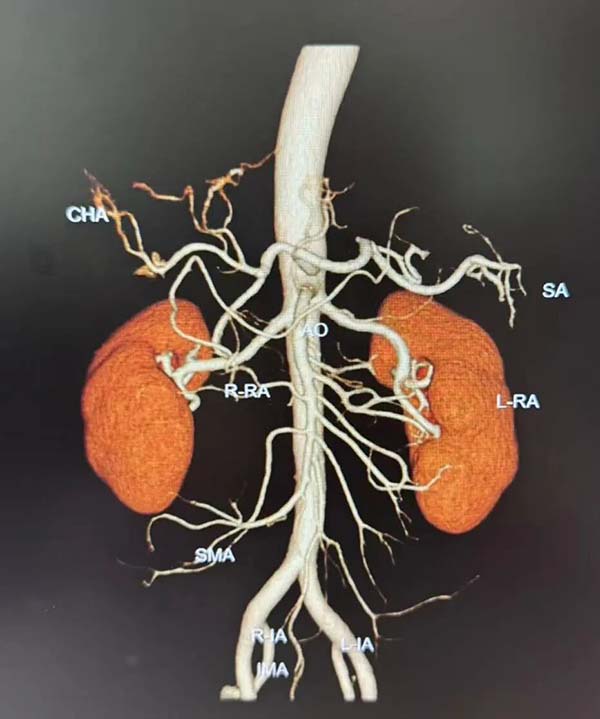

北京朝阳医院高血压专科团队对丘先生进行了门诊初筛及病房系统评估,完善肾动脉CTA三维重建、继发性高血压排查等相关检查后,最终明确诊断为原发性难治性高血压。赵林团队综合研判后认为,该患者具备RDN手术适应证,且肾动脉解剖条件优越——双肾动脉走形正常、管腔通畅,无明显狭窄及副肾动脉,为后续导管介入操作奠定了坚实基础。

肾动脉CTA三维重建影像